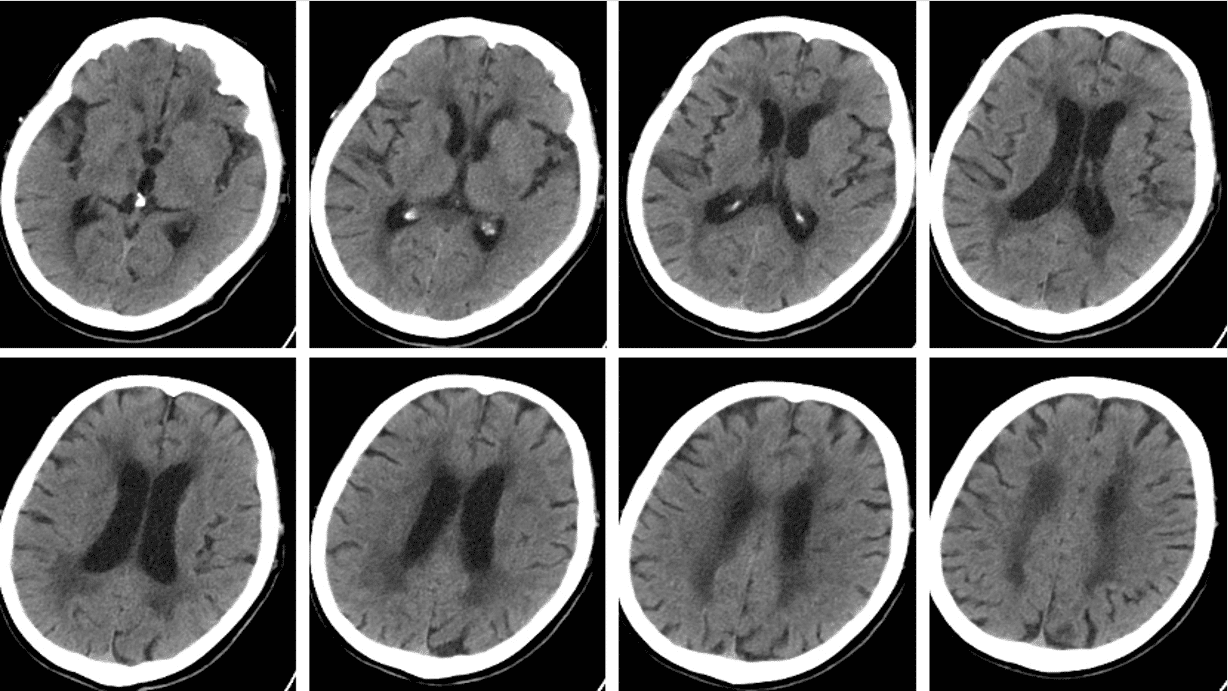

头CT(2025-7-9 7:40 急诊):脑内多发脑梗塞;双侧缺血性脱髓鞘改变;老年脑改变;副鼻窦炎症。

头CT(2025-7-9 13:40 本院)提示右侧颞叶、基底节区、顶叶及额叶高密度影,且破入侧脑室,考虑静脉溶栓后出血转化P2型。

⏰ 基于多田公式,粗测出血量>75ml,联系神经外科,建议手术,鉴于颅内存在动脉瘤,风险极高,家属拒绝手术方案。内科启动甘露醇联合利尿剂脱水、氨甲磺酸止血治疗,积极预防及治疗并发症。

动态观测CT变化,颅内出血及水肿情况经历 起病⇢进展⇢高峰⇢消退 动态变化,患者意识由昏迷逐渐转为嗜睡状态。三、临床诊断